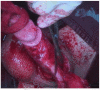

Methods: A systematic review of the literature from 1956 to 2022 was conducted in accordance with the general guidelines recommended by the Primary Reporting Items for Systematic Reviews and Meta-analyses (PRISMA) statement. We included full papers published from 1956 to 2022. We also described a case report of a 23 year old Bulgarian male affected by penile paraffinoma who underwent a 2-stages surgical technique.

Results: A total of 152 cases have been reported, with a median age of 37.9 ranging from 18 to 64 years. Six different techniques have been described in the whole literature: bilateral scrotal flap, simple excision of the paraffinoma with primary closure, two-stage scrotum skin flap, medial prepuce-soprapubic advancement flap technique and penile reconstruction using split thickness skin graft (STSG) or full thickness skin graft (FTSG). An analysis of the distribution among early and late complications was then carried out.

Conclusion: In our experience, among the variety of surgical techniques described, a two-stage penile reconstruction using scrotal skin results in excellent cosmetic and functional outcomes, with a low rate of complications.